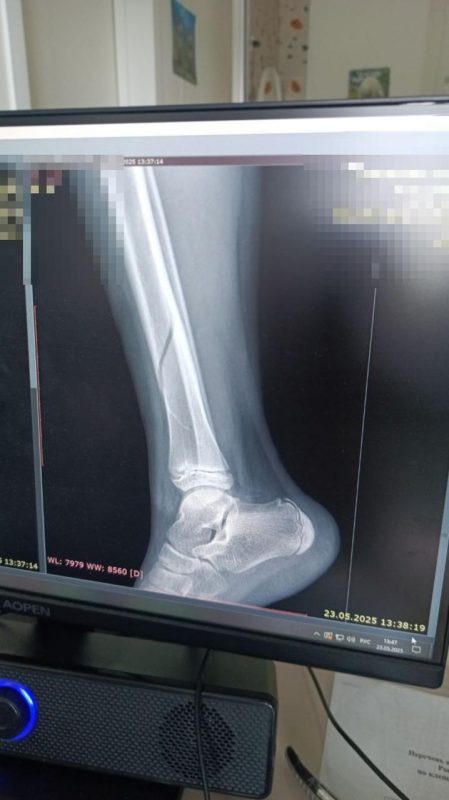

После того, как девочка выбралась из раздевалки, она, естественно, бросилась к своим обидчицам. Но хулиганки подставили ей подножку и Александра упала. Как отмечает Мария, мама пострадавшей, была не только подножка, но и удар ногой. В итоге у девочки диагностировал серьезный перелом берцовой кости. Сейчас пострадавшей приходится передвигаться на инвалидной каталке, так как такие переломы болезненны и долго срастаются. Мама Александры в тот же день написала заявление в полицию.